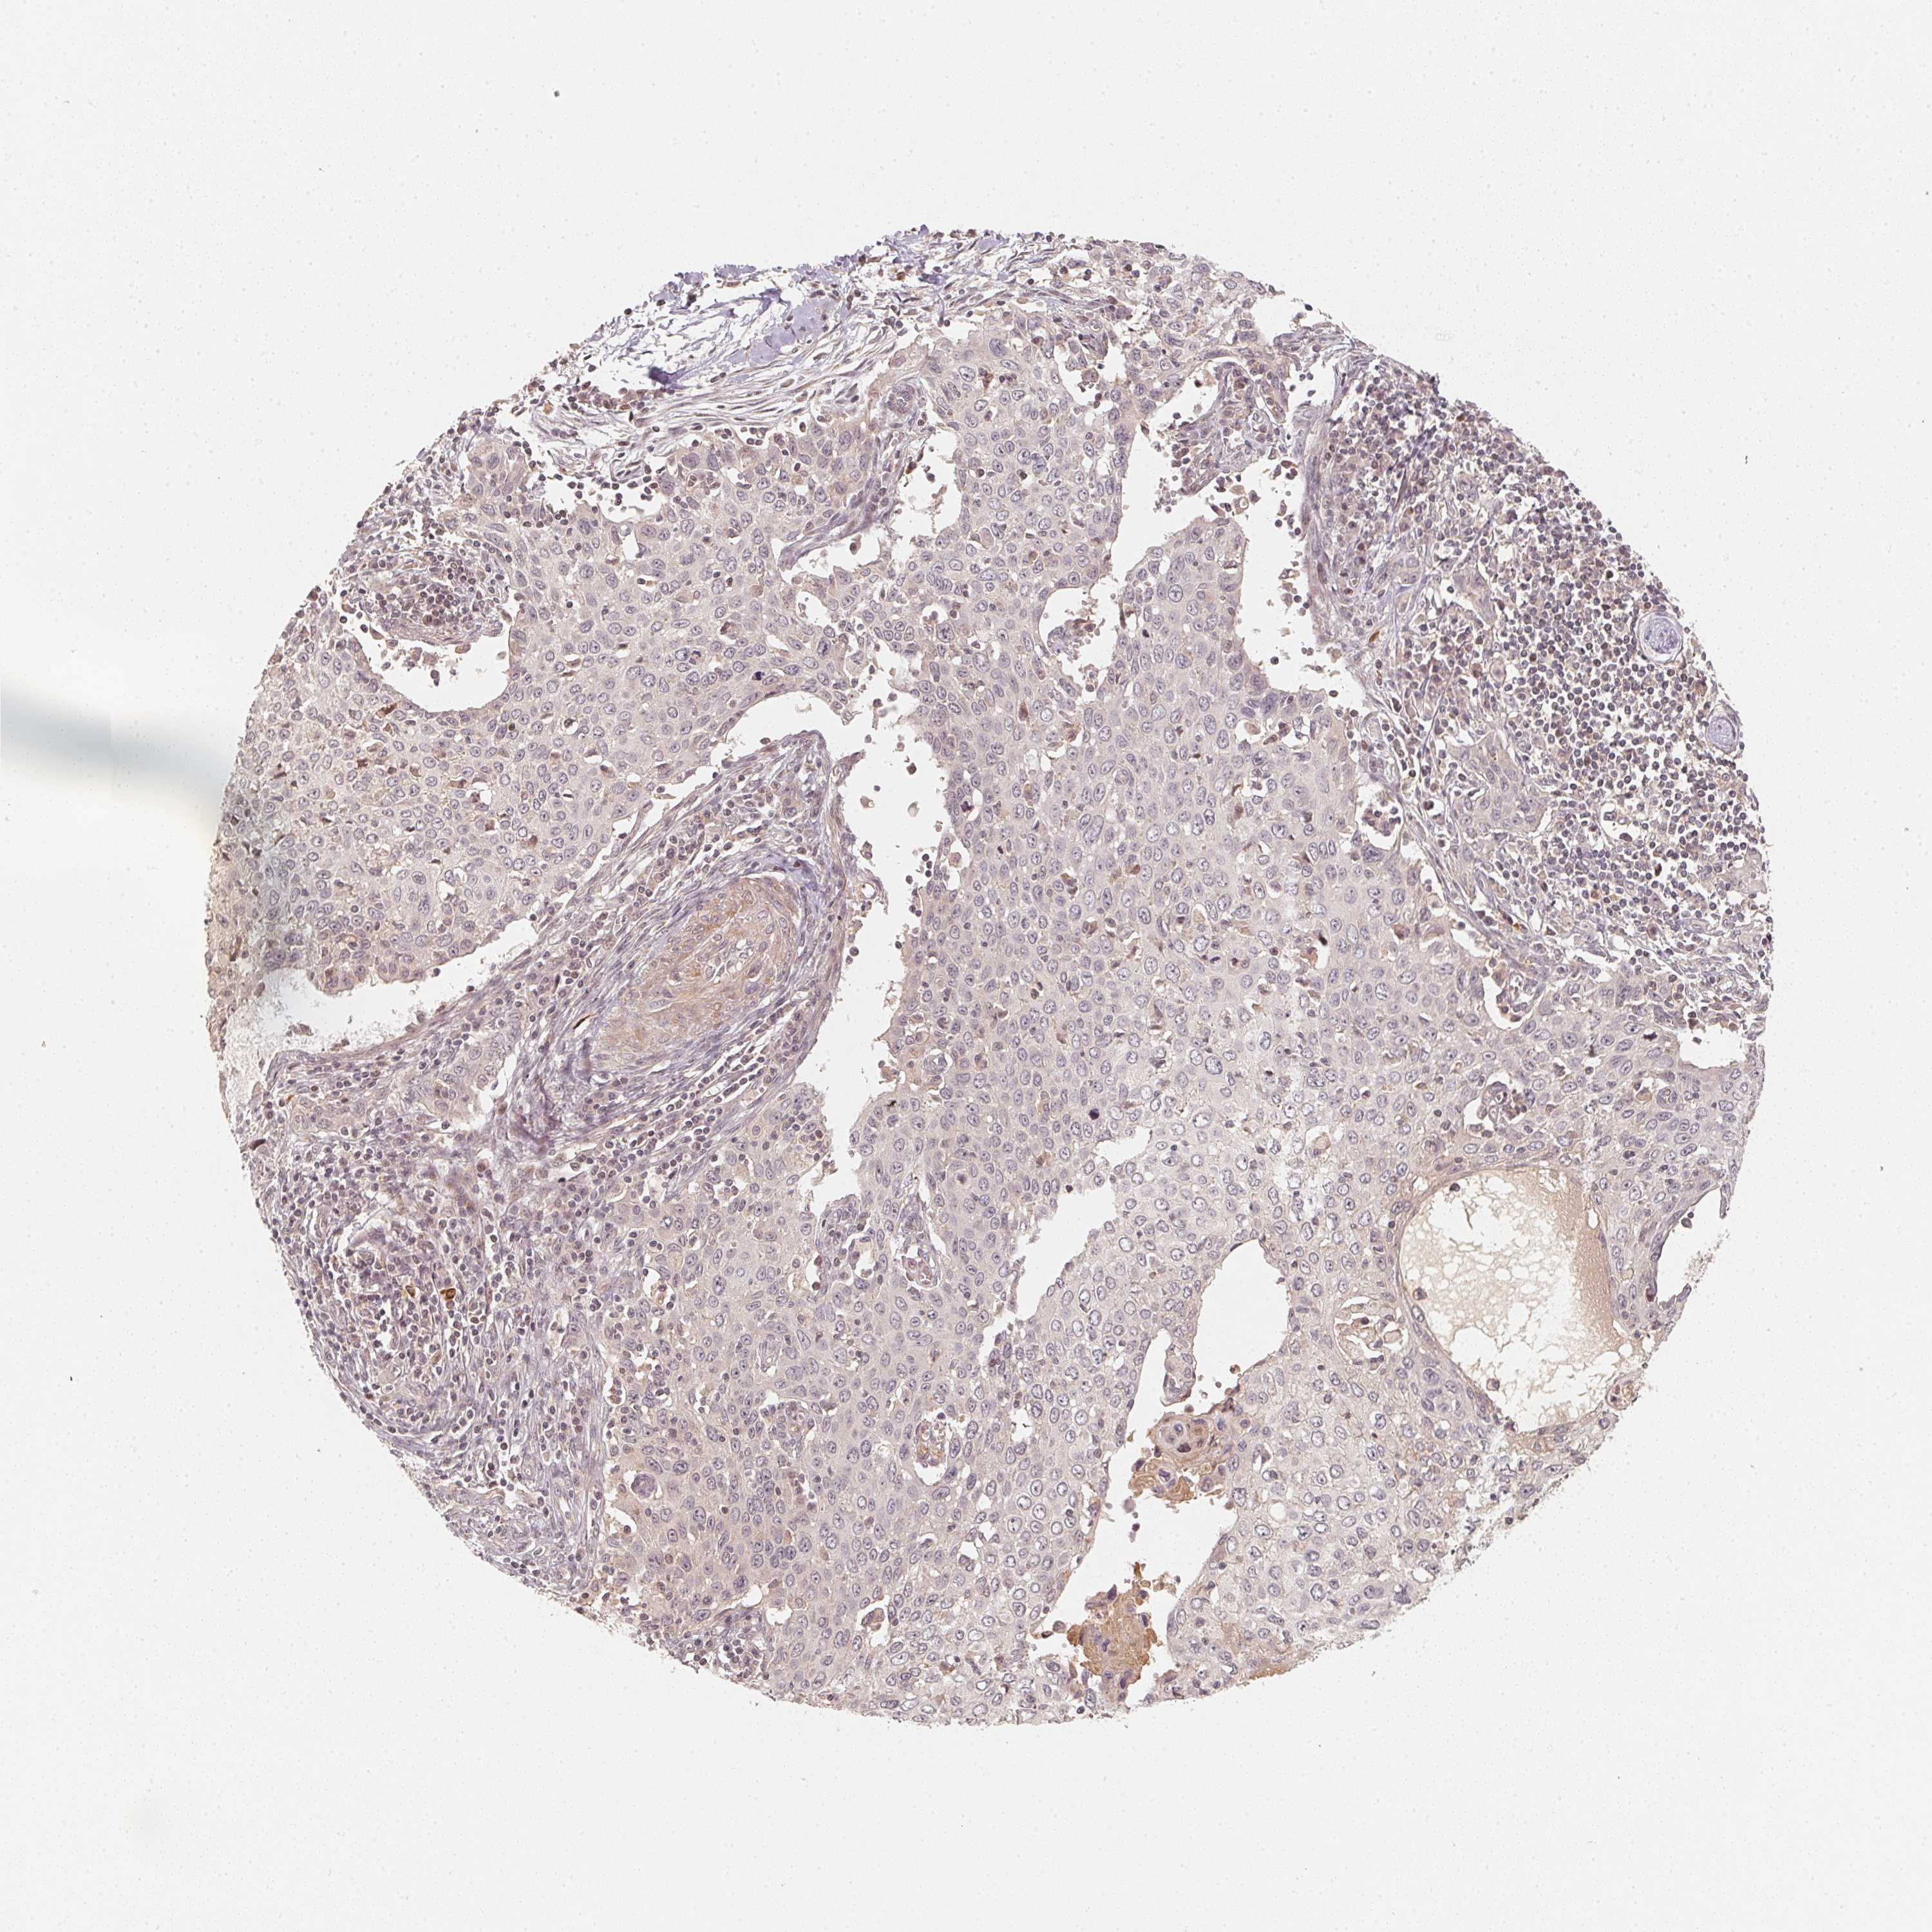

CERVICAL CANCER - Protein expressioni

A mouse-over function shows sample information and annotation data. Click on an image to view it in a full screen mode. Samples can be filtered based on level of antibody staining by selecting one or several of the following categories: high, medium, low and not detected. The assay and annotation is described here.

Note that samples used for immunohistochemistry by the Human Protein Atlas do not correspond to samples in the TCGA dataset.

Antibody stainingi

Antibody staining in the annotated cell types in the current human tissue is reported as not detected, low, medium, or high, based on conventional immunohistochemistry profiling in selected tissues. This score is based on the combination of the staining intensity and fraction of stained cells.

Each image is clickable and will lead to virtual microscopy that enables deeper exploration of all samples and also displays staining intensity scores, fraction scores and subcellular localization as well as patient and tissue information for each sample.

Antibody CAB068501

Staining

High

Medium

Low

Not detected

Intensity

Strong

Moderate

Weak

Negative

Quantity

>75%

75%-25%

<25%

None

Location

Nuclear

Cytoplasmic/membranous

Cytoplasmic/membranous,nuclear

Squamous cell carcinoma, NOS

Adenocarcinoma, NOS